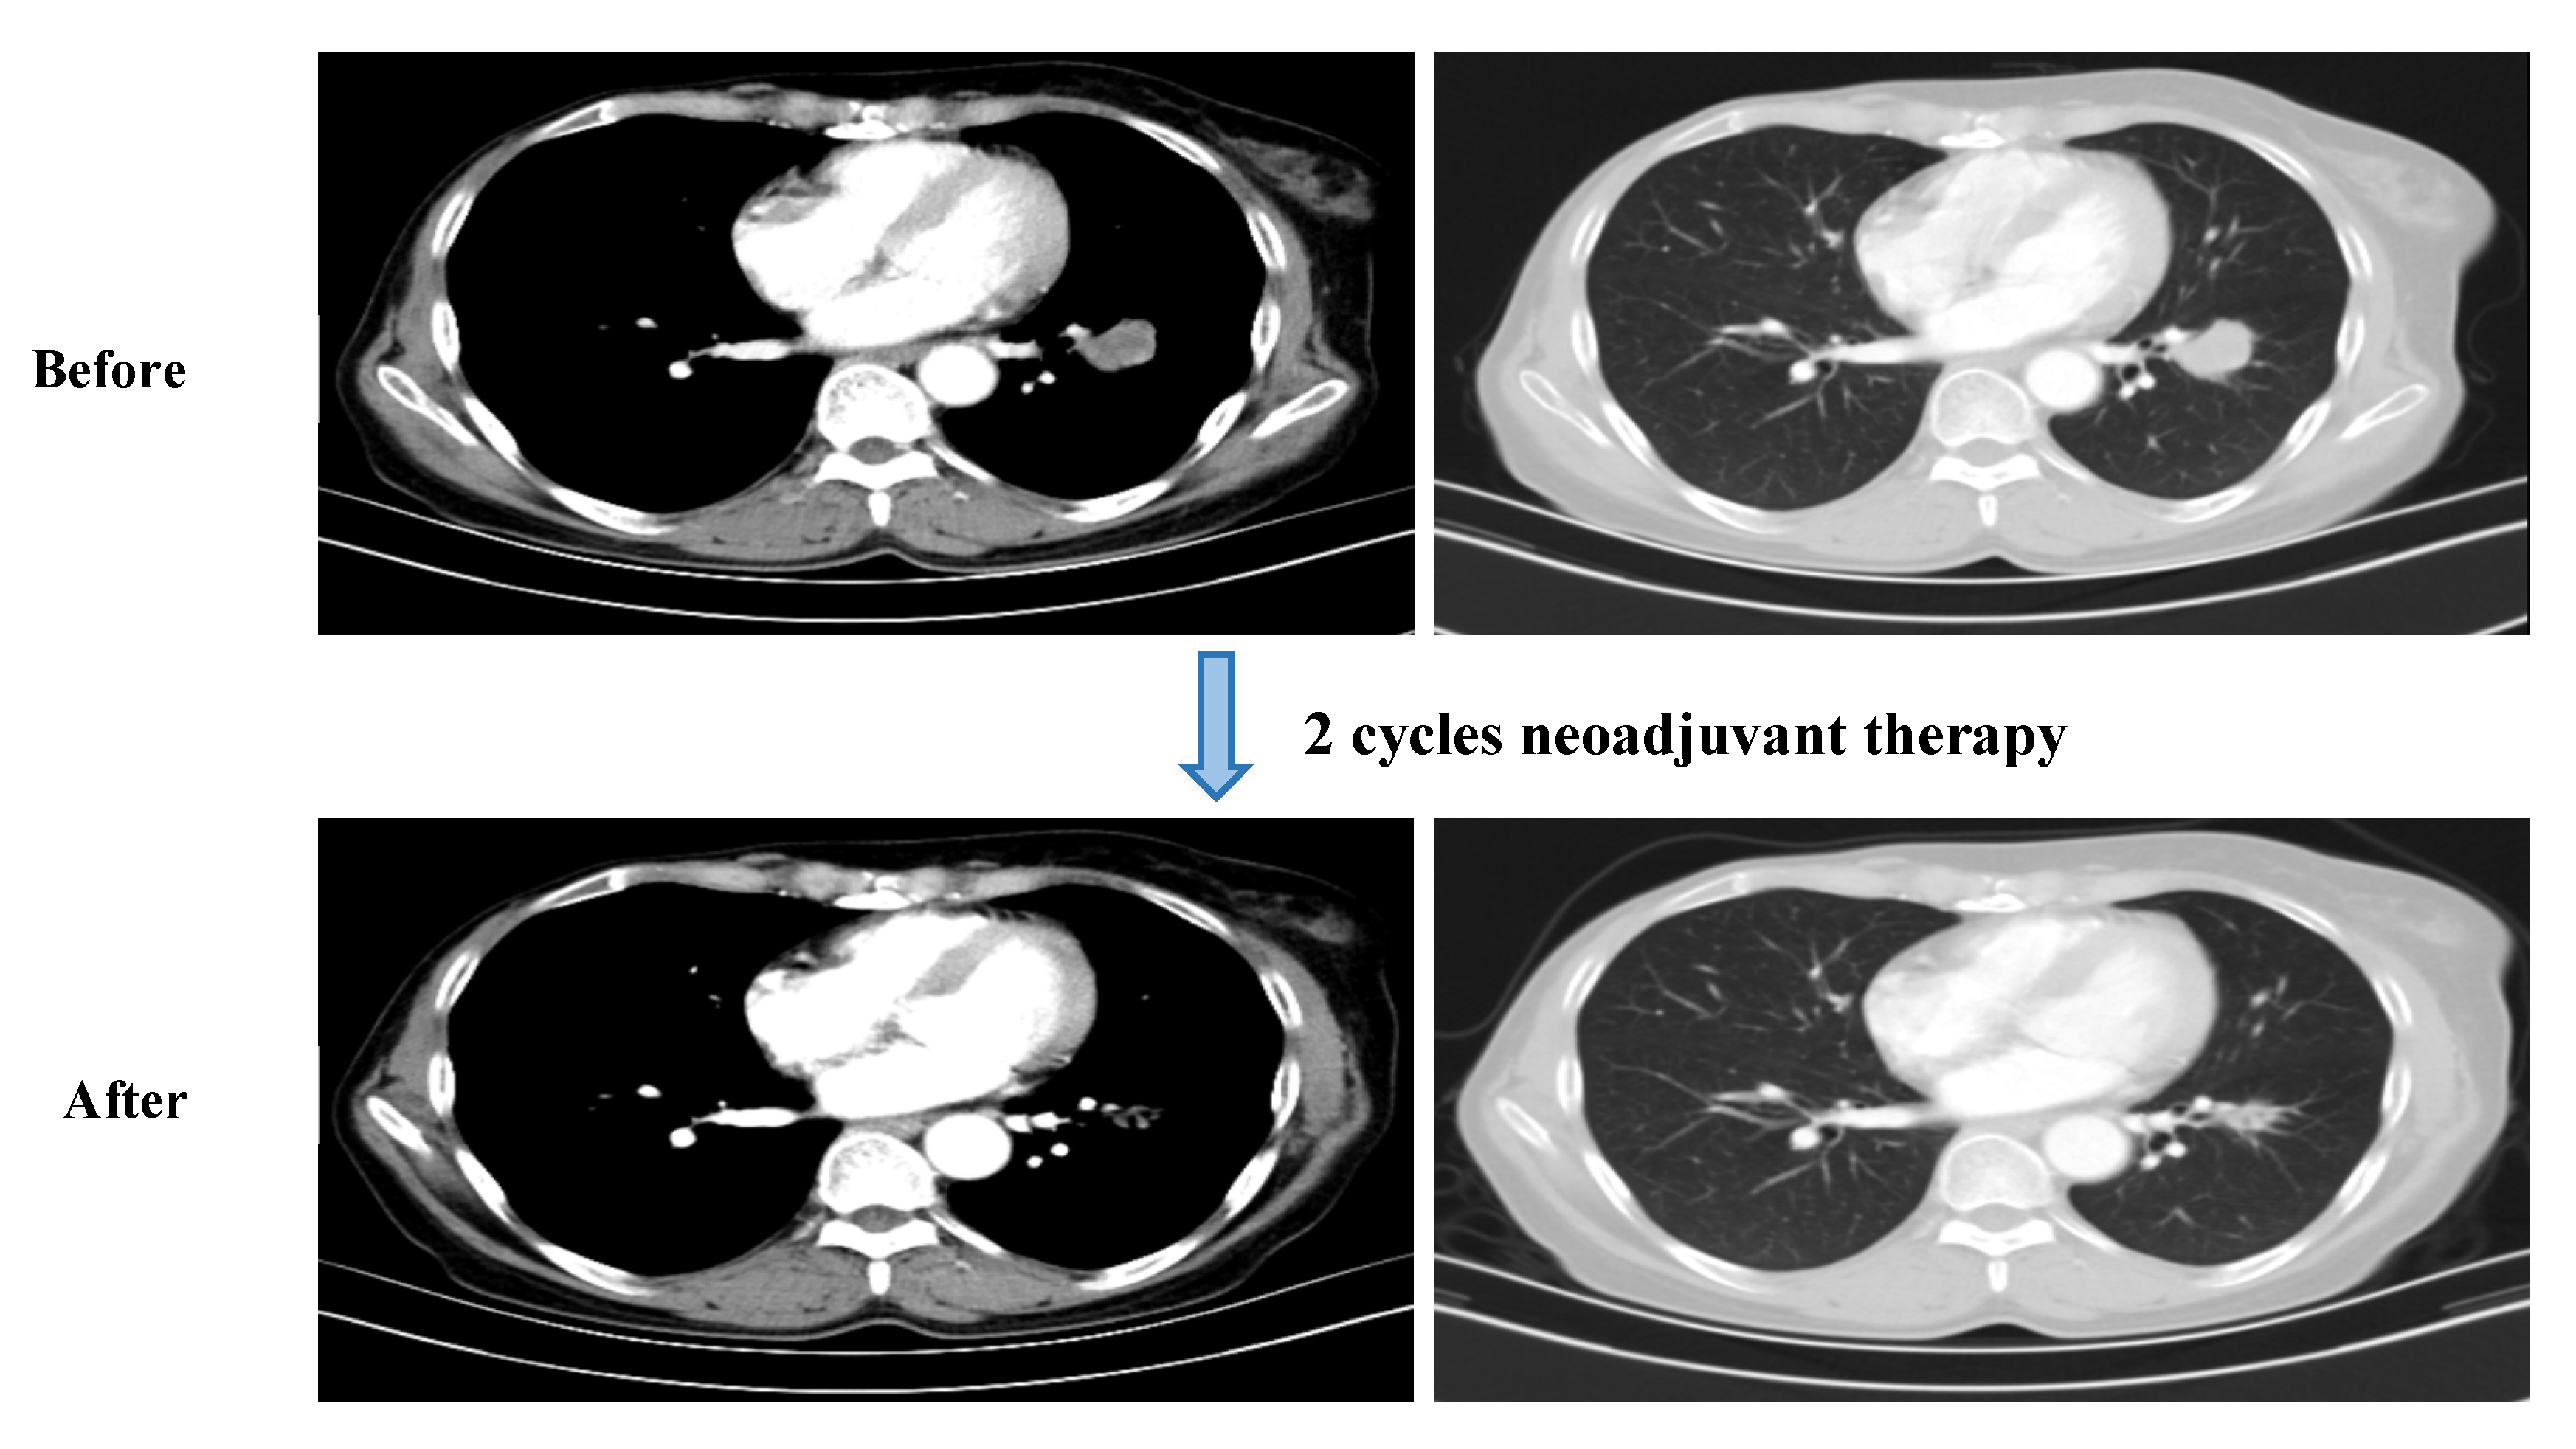

2. Case Presentation